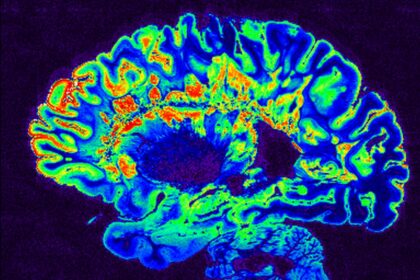

Η καλή είδηση είναι ότι η ανασφάλεια δεν είναι αναπόφευκτη ή ανυπέρβλητη. Με την κατάλληλη ψυχολογική υποστήριξη και τεχνικές όπως η Γνωσιακή Συμπεριφορική Θεραπεία, τα άτομα μπορούν να αλλάξουν τον τρόπο που σκέπτονται και να αντιμετωπίσουν τις προκλήσεις με μεγαλύτερη ανθεκτικότητα. Ο επαναπροσδιορισμός του τρόπου με τον οποίο ο εγκέφαλος εκλαμβάνει την ανασφάλεια αποτελεί κλειδί για την ψυχική υγεία και την προσωπική ανάπτυξη.